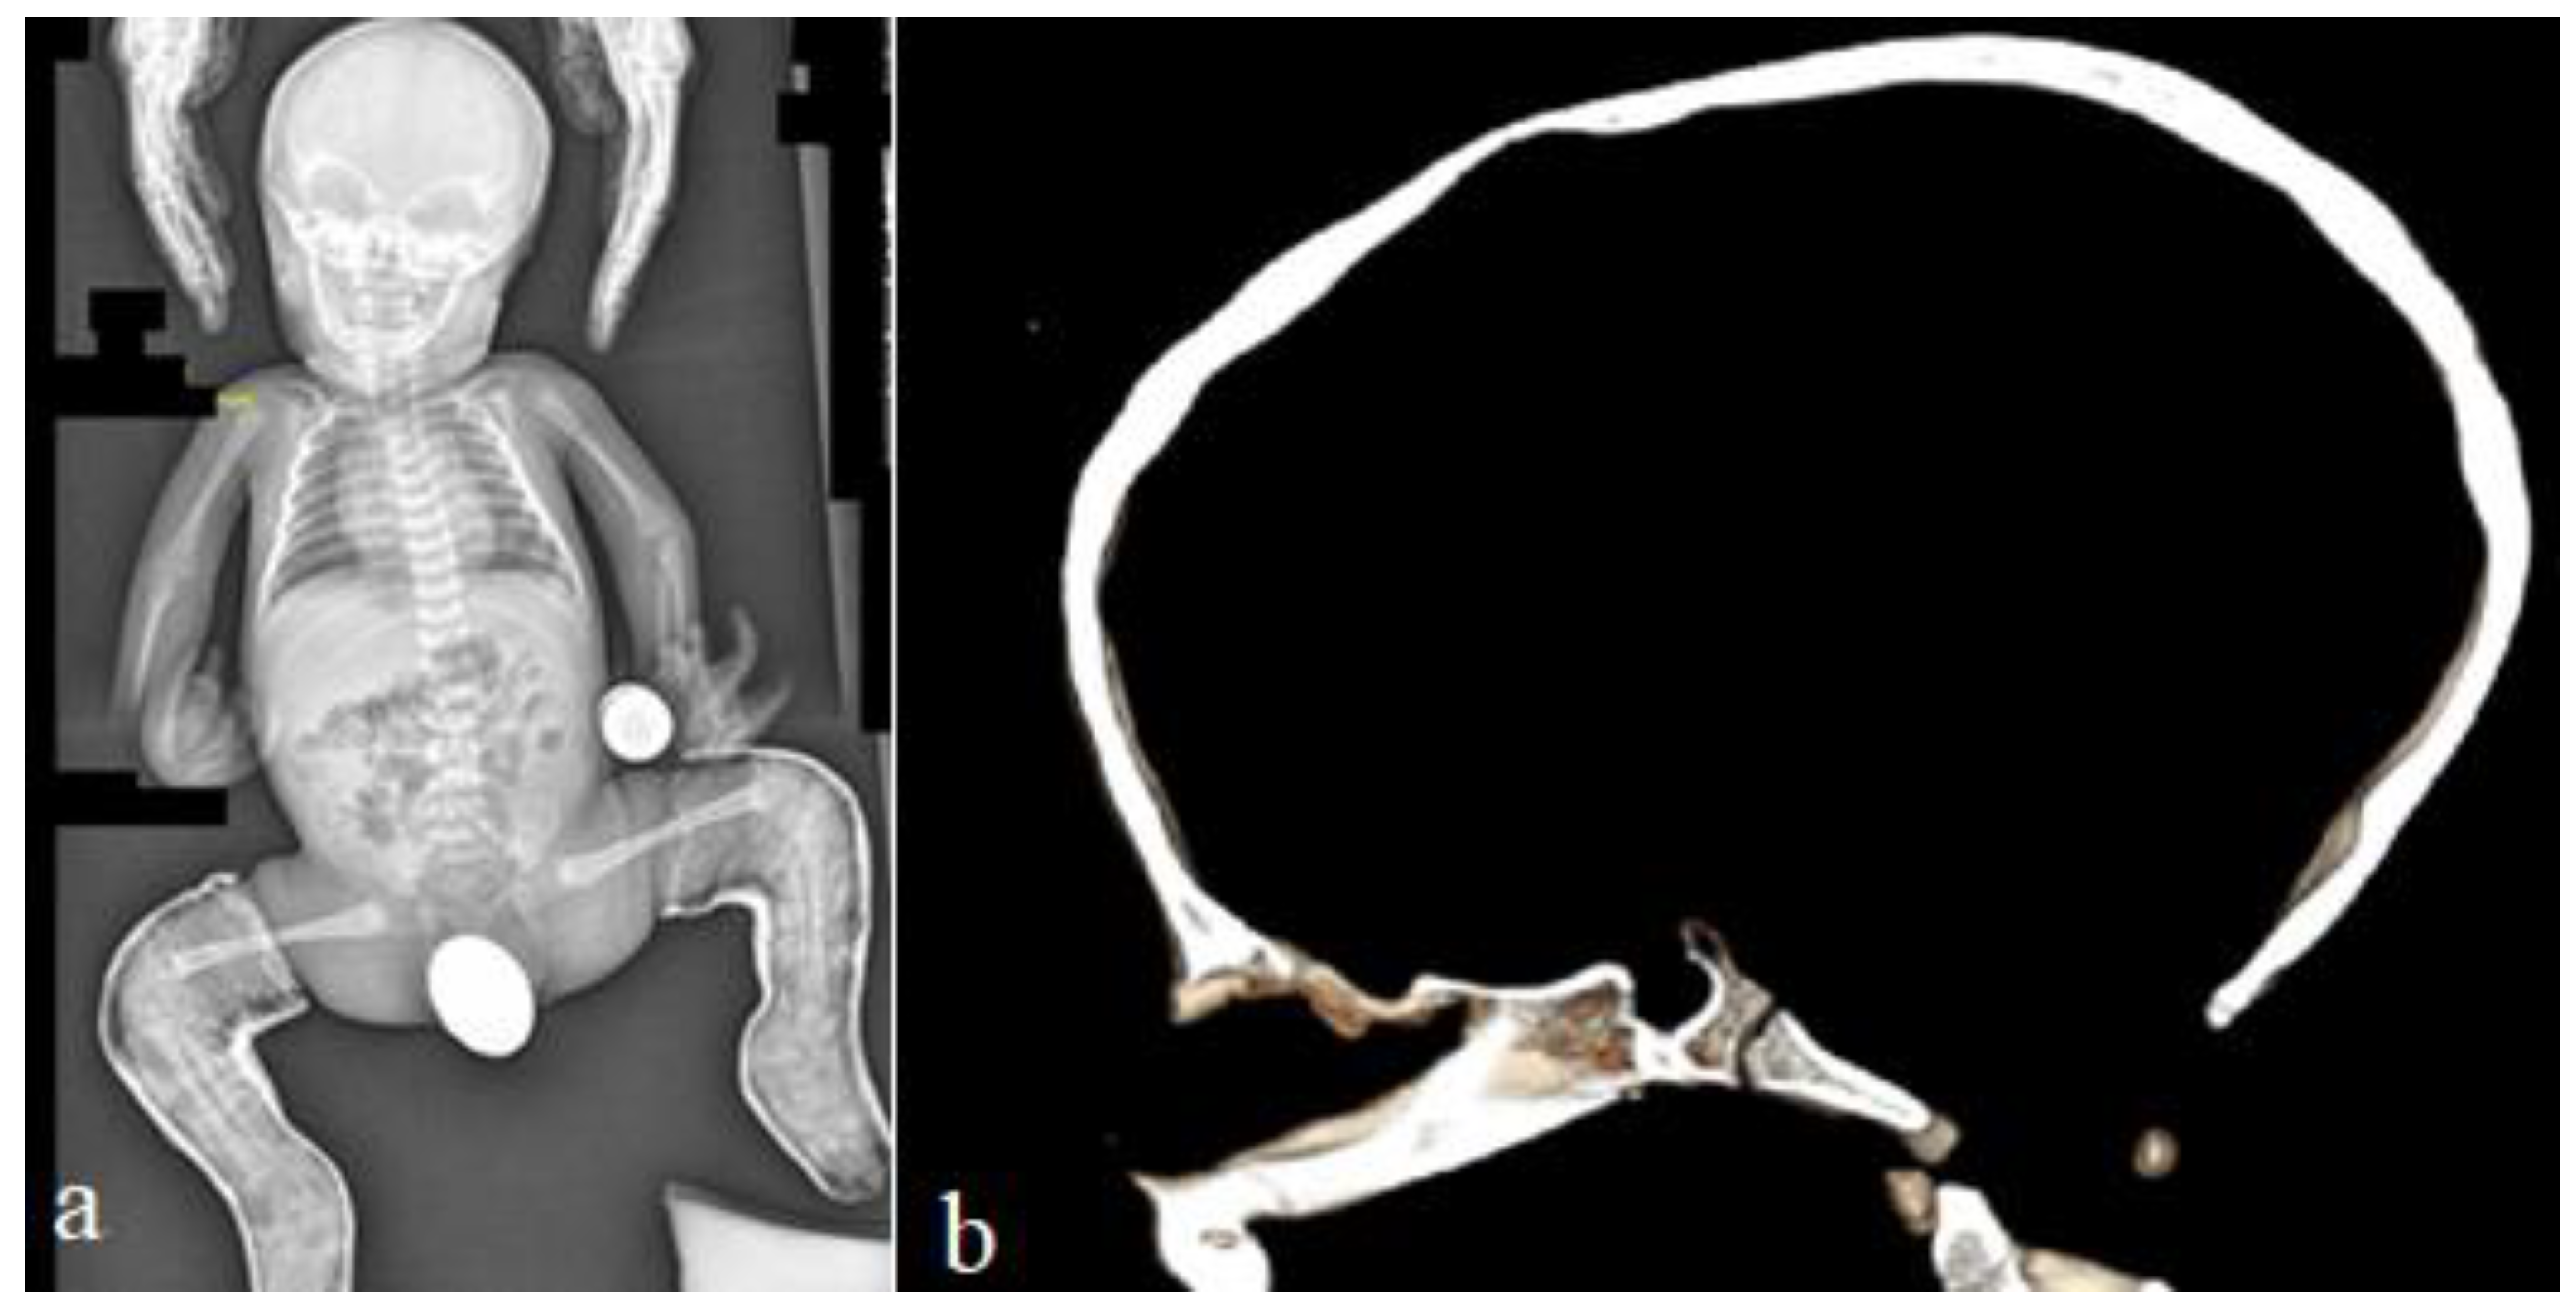

Two unrelated girls (4 years old and 12 years old) presented with multiple contractures. The 4-year-old girl presented with specific craniofacial features, marfanoid habitus and arachnodactyly. She was born full term as a product of non-complicated gestation. At birth, she manifested a crumpled irregular superior helix associated with multiple joint contractures, involving the fingers, knees, hips and elbows, and scoliosis. Her subsequent course of development was characterized as being awkward. The clinical phenotype of a 4-year-old-girl showed marfanoid habitus, a long face with a large and wide frontal area, hypertelorism, marfanoid-like features (thin and long slender limbs), kyphoscoliosis (arrow), long fingers (arachnodactyly) and apparent bilateral pes equinovalgus. The head was brachycephalic, with a long philtrum and a high vault palatine (Figure 6a). The ears showed specific abnormalities (the helix was flattened and crumpled, with some loss of the architecture (arrow)) (Figure 6b). A photo of the hands showed arachnodactyly and camptodactyly of the 5th fingers (Figure 7a). AP and lateral spine radiographs showed kyphoscoliosis (Cobbs angle of 80°) (Figure 7b). The 12-year-old girl was referred because of progressive scoliosis associated with multiple contractures. Three-dimensional phenotype reconstruction was applied to explore the skeletal system in full detail. She manifested the full clinical criteria of Marfan-like syndrome: long, thin limbs, arachnodactyly, multiple contractures and principally kyphoscoliosis, with a Cobbs angle of 90° (Figure 8a). A 3D reconstruction carried out to explore the crown of the skull showed asymmetrical development associated with closure of the sagittal suture (arrow), while the posterior part was somehow still preserved (arrow) (Figure 8b). Whole exome sequencing revealed a heterozygous mutation in the FBN1 gene (OMIM 134797) in both patients.

Figure 8. A 12-year-old girl was referred because of scoliosis associated with multiple contractures. Three-dimensional phenotype reconstruction was applied to explore the skeletal system in full details (a). She manifested the full clinical criteria of Marfan-like syndrome (a). Long, thin limbs, arachnodactyly, multiple contractures and principally progressive kyphoscoliosis, with a Cobbs angle of 90° (a). Three-dimensional reconstruction carried out to explore the crown of the skull showed asymmetrical development associated with closure of the sagittal suture (arrow) (b).